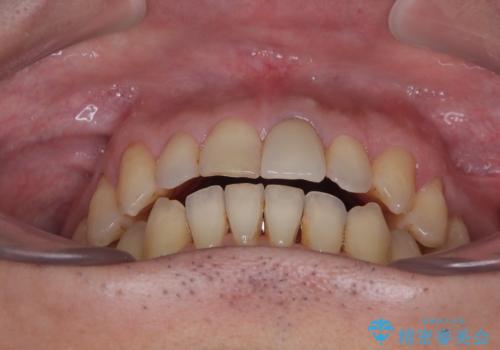

- 長年気になっていた口元を改善したいとのことで来院された患者様です。

外科手術を併用した矯正治療を検討するほどに隙間の空いた開咬と、顕著な叢生が認められました。

開咬の改善には、舌の突出癖改善のためにトレーニングを行いつつ、インビザラインでの矯正治療が大変有効ですが、上顎骨が下顎骨に対して前方位に位置しており、インビザライン単独で治療を行うよりは補助装置とワイヤー矯正で奥歯の咬み合わせを改善してから、開咬改善のためのインビザライン矯正治療を行うこととしました。